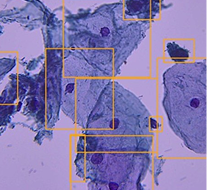

CervixScreen AI («Нейропасс»)

Продукт на основе ИИ, диагностирующий рак на ранних стадиях

Рынок онкоскрининга — один из самых быстрорастущих сегментов медицины, где эффективно внедряется ИИ.

Врачи-цитологи испытывают колоссальную нагрузку, анализируя более 100 мазков в день. На фоне усталости и разрозненности данных повышается риск врачебных ошибок при выявлении онкологии.

«Идея возникла из клинической практики. У врачей-цитологов высокая нагрузка. Получение визуальных данных и микроскопии часто разрозненно. В таких условиях качество диагностики часто зависит от большого количества факторов, в том числе субъективного опыта специалиста. В некоторых случаях врач анализирует более 100 мазков в день. Это повышает риск ошибок»

· Решение

Продукт на базе ИИ, который автоматизирует морфологическую диагностику. Технология объединяет анализ кольпоскопических и микроскопических снимков, позволяя врачу выявлять патологические изменения быстрее и точнее.

Снижение нагрузки на врачей и минимизация диагностических ошибок. Раннее выявление онкологии критически снижает затраты системы здравоохранения на последующее лечение и диагностику.

· Масштаб

Пилотные тесты на базе МСЧ КФУ подтвердили эффективность системы.

· Планы

Масштабирование архитектуры на колоректальный рак, рак гортани и заболевания крови. Выход на рынки стран с высокой потребностью в массовом скрининге: Индию, ЮАР и Бразилию.